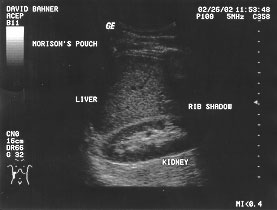

Hepatorenal space (labeled)